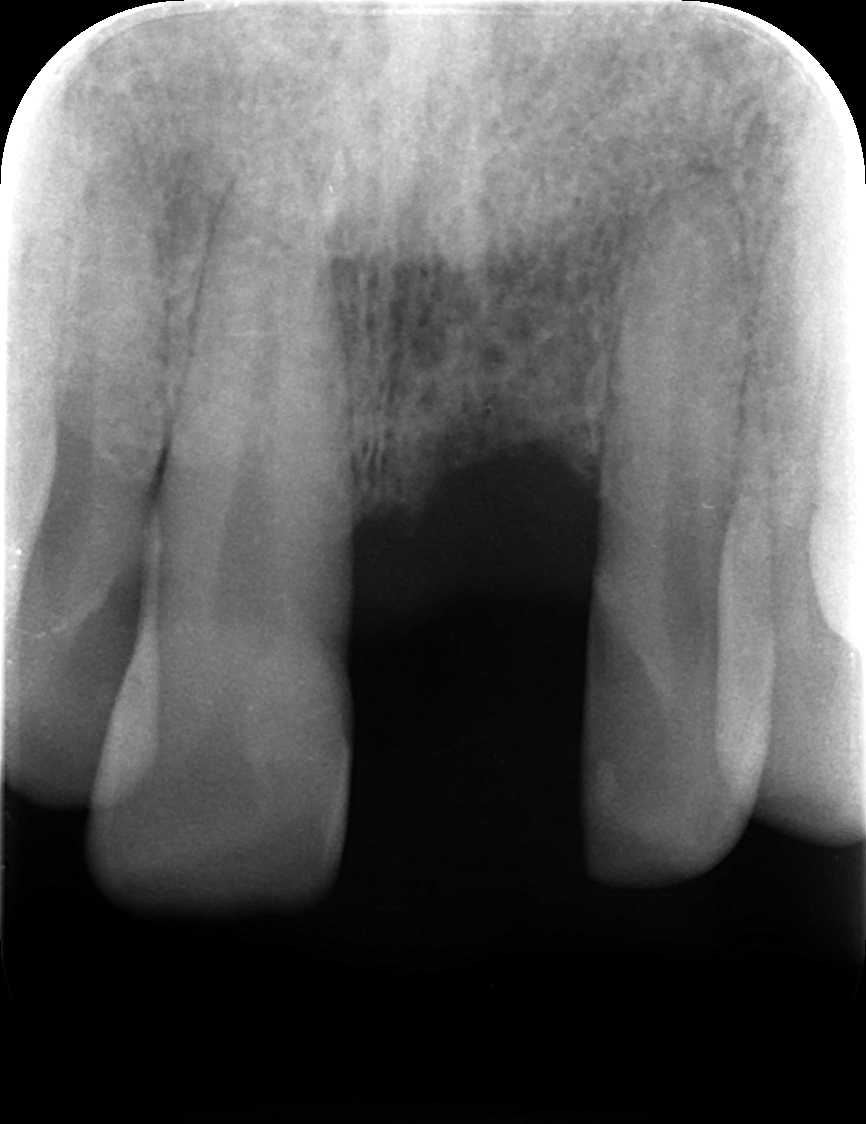

左下2本インプラント症例

主訴 奥歯でしっかり咬めるようにしたい(男性) 治療内容 左下の奥歯2本をインプラントにて治療しています。プラマRFインプラントを埋入。

手術後3ヶ月待ち、骨とインプラントが固まったことを確認し、二次手術後に型取りを行っています。当院では、ほとんどの症例でデジタルでの型取りを行っています。

インプラントを埋入した部位に型取り用のパーツをはめ、3Dスキャナーにて型取りをし、ジルコニアクラウンの被せ物を作製しています。完成後の咬合面は状態を確認後、埋めていきます。

治療期間 約4ヶ月

費用 総額 ¥700,000-(税別) リスクと副作用 ・外科治療となるので、お身体の状態によっては受けれない場合がある(広範囲に適用可能な治療ですが、個々の患者様の状況によって適用外な場合もある)

・術後に多少の痛みや腫れが出ることがある -